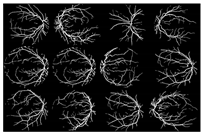

I applied the preprocessing method to all datasets, which had been normalized and enhanced for the coarse extraction stage. Then, I used the WKFCM for 9 (m = 1, 2, 3, 5, 7, 9, 11, 12, 13) with different random initialization processes of the membership values of an object to all classes in the dataset. For random initialization for the kernel function, I used three kernel function values (σ =0.3, 0.5, 0.7) of the adjustable parameter, σ, of the Gaussian kernel function to find the optimized result out of the three. Next, I provided the optimized values of the number of clusters for five different validity measures (c = 1, 2, 3, 4, 5) for the best choice among five values of the WKFCM obtained in 150, the maximum number of iterations. Finally, an initial threshold value (T) of 120 was selected as the minimum value to classify the histograms between the two classes. The blood vessel extracted using the proposed WKFCM method is illustrated in Figure 7. Three retinal images from the DRIVE, STARE, and DiaretDB0 databases are displayed in Figure 7.

Figure 7.

Examples of retinal blood-vessel extraction: (a) the result of the direct WTH, (b) retinal blood vessels extracted by the proposed WKFM, (c) the image after intensity thresholding. From the top (DRIVE), middle (STARE), and bottom (DiaretDB0).